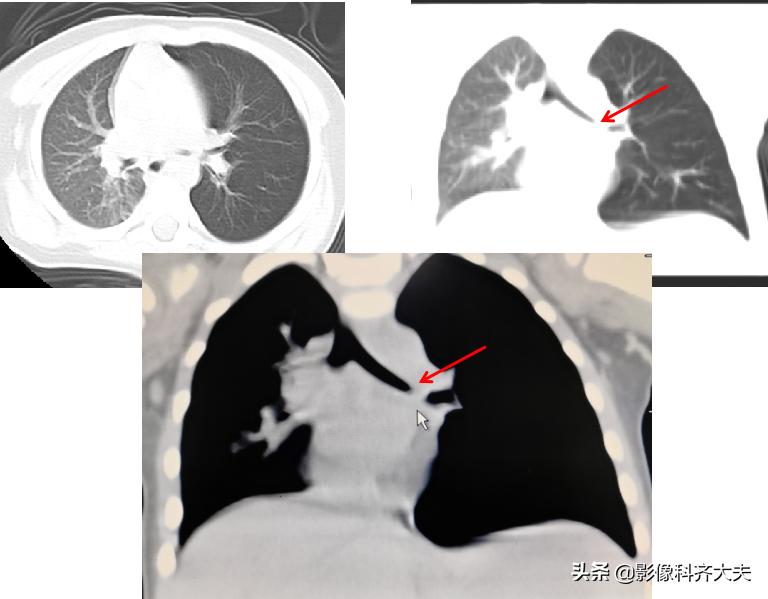

图为轴位及冠状位重建图显示异物:红色箭头为异物的位置,冠状位显示尤为清晰。

轴位显示左侧支气管疑似异物,红色箭头。

冠状位重建清晰显示左侧支气管异物,红色箭头所示。

最小密度投影显示的更加清楚。

图中CT轴位扫描及MPR冠状位重建,清晰显示左左侧支气管异物,红色箭头所示。